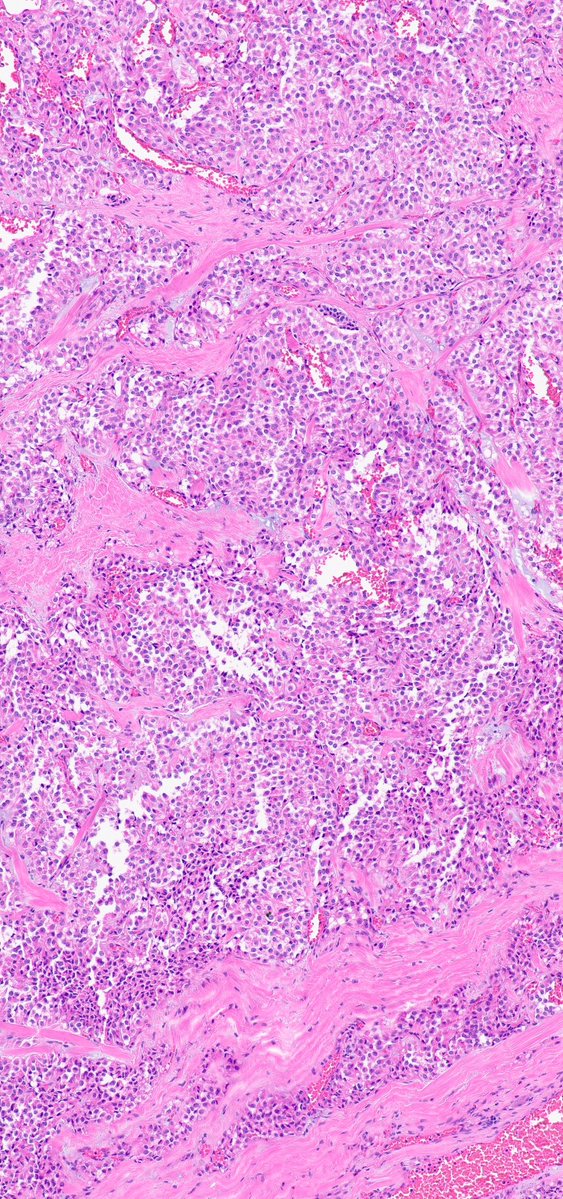

#PathX #PathTwitter #BreastPath #USCAP2026